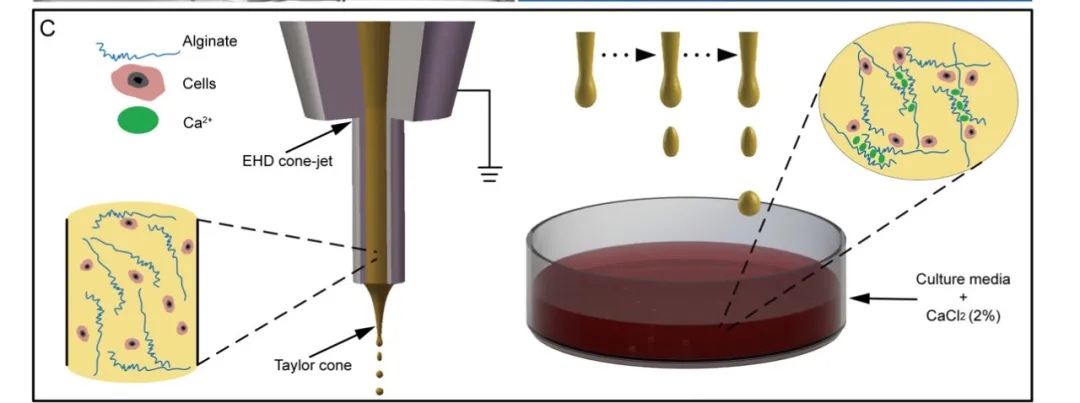

非粉末床金属增材制造综述 生物3D打印载细胞微球治疗